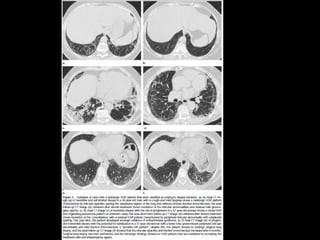

UIP TC • Fibrosiscon áreas normales. • Disminución de volumen pulmonar • Opacidades reticulares • Vidrio esmerilado • Predominio en regiones basales y subpleurales • Distorsión arquitectónica con bronquiectasias por tracción secundaria a fibrosis. • Panal de abejas (2-20mm) • Linfoadenopatías mediastínicas pequeñas.

DD UIP CT •AR, Esclerodermia (esófago dilatado) • Asbestosis ( derrame pleural, bandas parenquimatosas) • Neumonitis por hipersensibilidad crónica: fijarse en signos de atrapamiento aéreo, Respeto de bases o cuando hay nódulos centrolobulillares. • Sarcoidosis terminal: fibrosis en segmentos posteriores de lóbulos superiores o perihiliar, o nódulos perilinfáticos. • NSIP • Complicaciones: • Exacerbación, DAD • Cáncer pulmonar 10-15% bases

NSIP TC • Vidrioesmerilado bilat y simétrico, LS Reticulación fina, BQ por tracción, disminuciónd e volumen pulmonar, panalización leve Consolidaciones Exacerbaciones menos comunes que FPI • Pronóstico depende del grado de fibrosis • Celular: 100% sv Fibrótico: 5 años SV